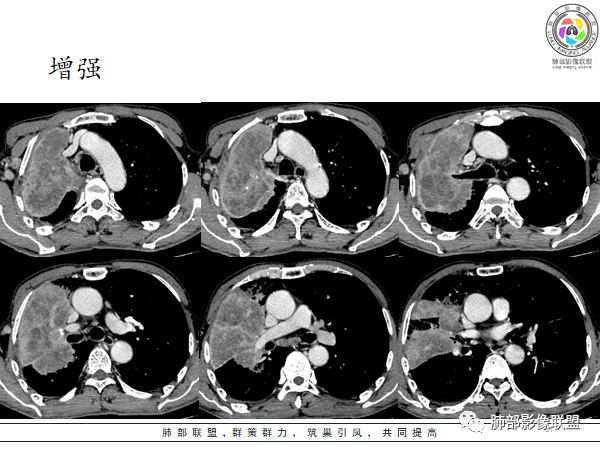

南边老师分析

我说一下征象,判断这类病变,首先应该考虑:炎性、恶性肿瘤

如果没把握,我们就从恶性出手。

恶性这类分析思路:整个是肿瘤?腔内肿瘤?

肺动脉走形自然

如果近端中央型肺癌,肺动脉破坏明显——所以晨读病例不支持中央型肺癌。

下图:这是中央型肺癌的特点:肺动脉破坏。

腔内肿瘤?肺动脉没有推移,累及多段

远端不是阻塞性不张,不支持腔内肿瘤

然后就是外朝内肺炎型肺癌或者炎性

远端支气管是通畅的,只是腔内粘液栓